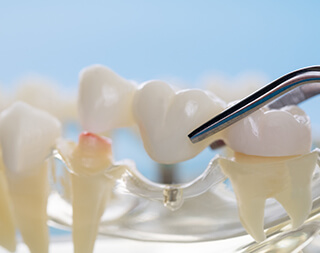

ブリッジ

欠損歯が1~2本くらいで、その隣接する健全な歯を利用して橋を渡すように義歯を作ります。義歯に見えにくい利点があります。